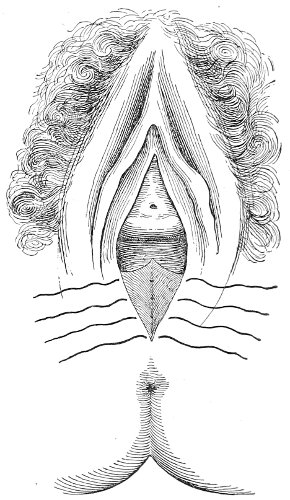

Slight Median laceration of the Perineum.—In this injury the tear takes place through the fourchette. Posteriorly it may extend as far as the sphincter ani muscle. Upward it may extend for an inch up the posterior vaginal wall. The appearance of this tear is shown in Fig. 33. It will be noted that, as this tear takes place in the median line, none of the muscles that support the perineum are involved, nor are the planes of fascia injured. The perineum is slightly split, and the insertions and origins of the muscles and the fascia are slightly separated. The supporting structures of the perineum and the pelvic floor are, however, uninjured.

Fig. 33.—Recent slight median laceration of the perineum: sutures introduced.

If this tear is detected after labor, it should be closed by the immediate operation. A slight tear involving chiefly the cutaneous aspect of the perineum should be closed by three or four sutures introduced from the outside, as in Fig. 33. The needle should be introduced about a quarter of an inch from the edge of the wound. It should not be passed parallel with the plane of the lacerated surface, but should be swept outward and then inward toward the 68 angle at the bottom of the tear (Fig. 34). It may either emerge at the angle and be re-introduced, or it may be passed directly through to the skin-margin on the opposite side of the wound. If the suture is passed in this way, there will be perfect apposition throughout the whole surface of laceration. If the sutures are improperly passed, there may result only apposition of the skin-edges.

If the laceration extends up the posterior vaginal wall, two sets of sutures must be introduced—one on the vaginal aspect of the tear, and one on the skin aspect (Fig. 35).